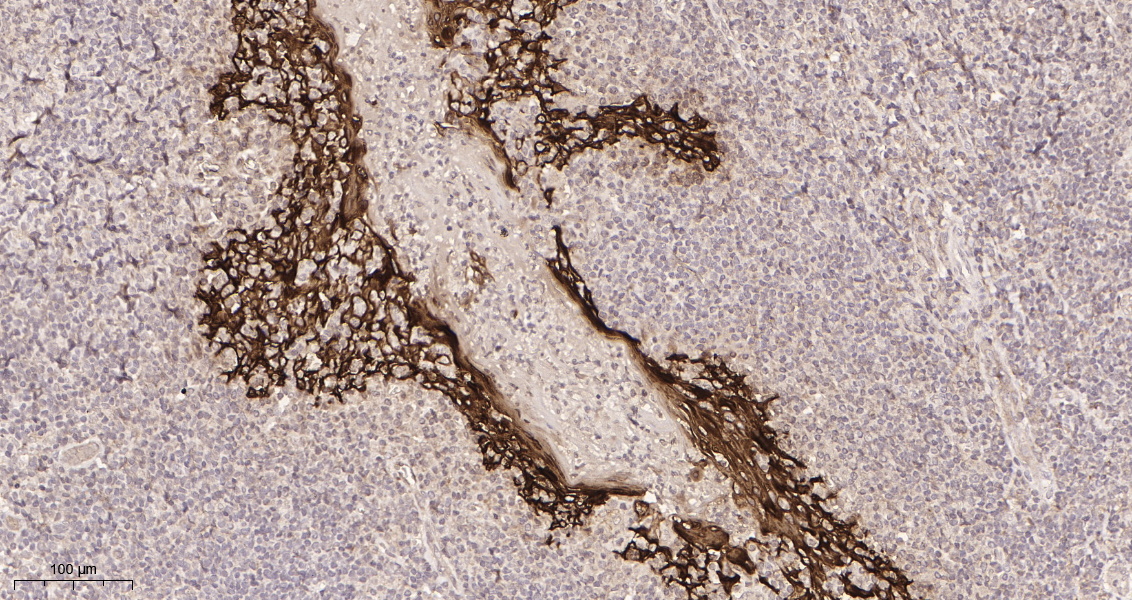

产品名称Cytokeratin 5 (10X11) Rabbit Monoclonal Antibody

推荐应用WB,IHC-P,IF-P,IF-F,IF-ICC,ELISA

稀释度IHC-P 1:200-1:1000, WB 1:1000-1:5000, IF-P/IF-F/IF-ICC 1:200-1:1000, ELISA 1:5000-1:20000

背景介绍keratin 5(KRT5) Homo sapiens The protein encoded by this gene is a member of the keratin gene family. The type II cytokeratins consist of basic or neutral proteins which are arranged in pairs of heterotypic keratin chains coexpressed during differentiation of simple and stratified epithelial tissues. This type II cytokeratin is specifically expressed in the basal layer of the epidermis with family member KRT14. Mutations in these genes have been associated with a complex of diseases termed epidermolysis bullosa simplex. The type II cytokeratins are clustered in a region of chromosome 12q12-q13. [provided by RefSeq, Jul 2008],